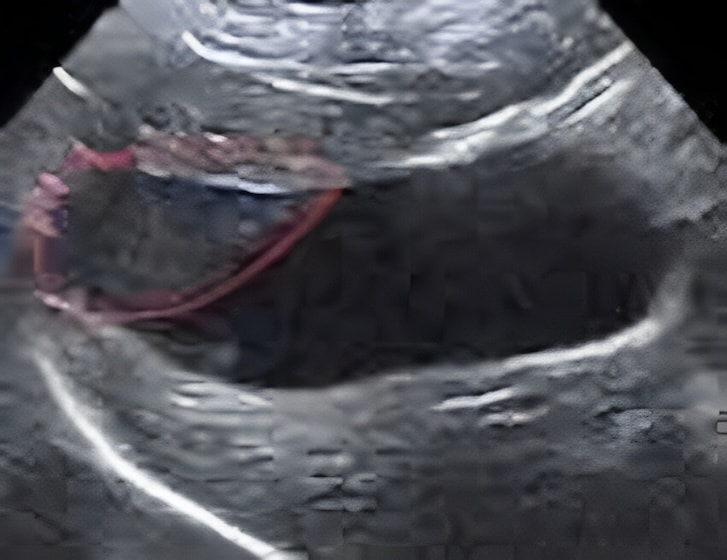

膀胱腫瘤(2025/11/25)

犬猫共に、膀胱内に腫瘤が発生することがあり、その場合には排尿しづらそうな様子や、血尿、頻尿といった、膀胱炎などと同様の症状がよく認められます。超音波検査を行うことで、膀胱内に腫瘤が形成されているかどうかを確認することが出来ます。また、カテーテルを用いて採材を行い、細胞診検査や遺伝子検査を行うことで診断を行います。診断後、腫瘤の発生状況などにより、外科的/内科的治療を検討していきます。膀胱内腫瘤を認めた場合には悪性腫瘍であることが比較的多いこともあり、普段と異なる排尿の様子が認められた場合などは、お早めにご相談下さい。

獣医師 池田